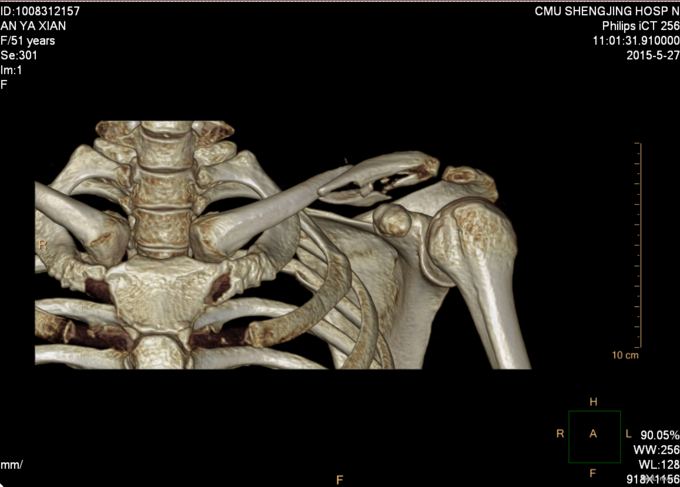

主诉:摔伤后左肩部疼痛活动受限18天 现病史:患者自述于2015-5-9日中午在沈阳市辽岛附近骑直行车时自己摔伤,左肩部着地,伤后患者左上肢疼痛活动受限,急诊送至沈阳市胸科医院,行左肩关节正位DR,提示为左锁骨骨折,患者于胸科医院保守治疗肋骨骨折13天,于2015-5-22日出院,现患者感觉左肩部疼痛,为求进一步治疗来到中国医科大学附属盛京医院创伤骨科,患者入科后神志清楚,饮食佳,无头晕头迷,无恶心呕吐,二便正常。

专科查体:患者左上肢吊臂带悬吊中,左肩关节肿胀,可见锁骨隆起,压痛(+),叩击痛(+),锁骨远端按压有浮动感,左上肢感觉正常,桡动脉搏动有力,末梢血运良

患者入院后完善检查,无血气胸,单纯锁骨骨折,择期行左锁骨粉碎性骨折切开复位内固定术,术后患者患肢悬吊中。术后患者14天拆线后出院。